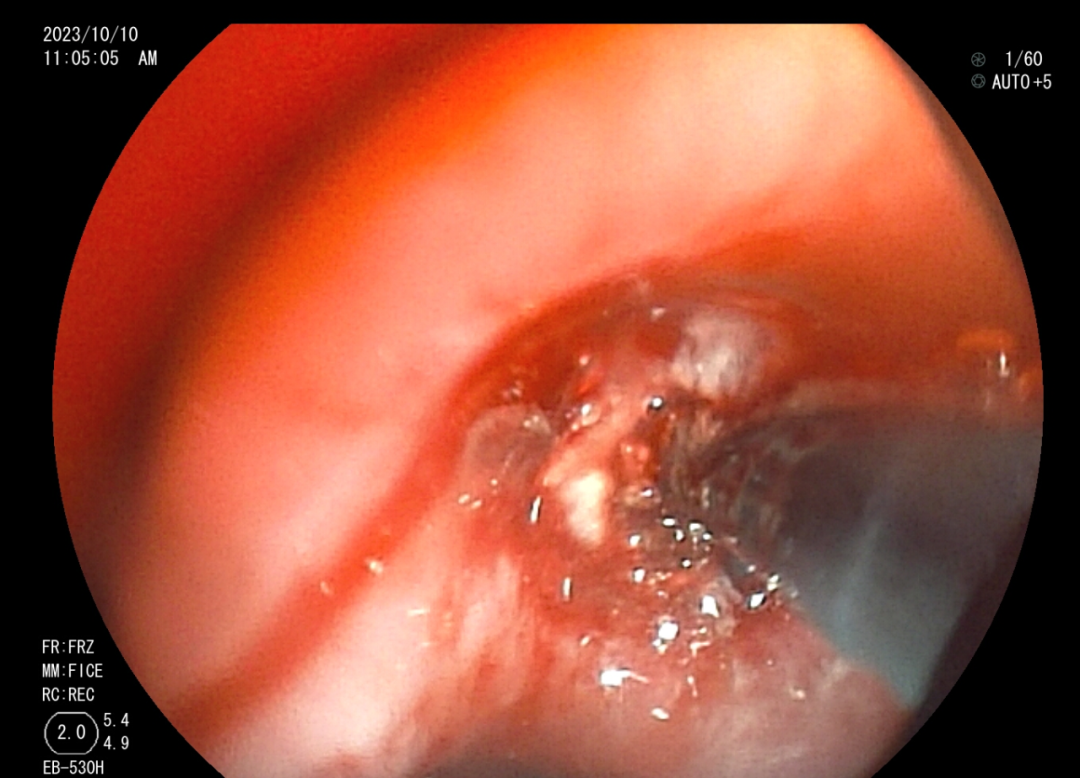

肺科醫(yī)院)住院治療。 10月10日,我院內(nèi)鏡中心為小邰進(jìn)行了第一次支氣管鏡檢查,檢查提示小邰左肺上葉可以看見巨大新生物完全阻塞管腔,充分評(píng)估后,行手術(shù)治療,手術(shù)中應(yīng)用了活檢鉗、異物鉗、冷凍、高頻電刀、內(nèi)鏡下超聲探頭等方法,既保證了患者的安全,又達(dá)到了治療目的,通過三次手術(shù),終于將左上葉巨大腫塊清除掉了。術(shù)后1周復(fù)查胸部CT小邰左肺上葉復(fù)張開來,感覺胸悶、氣促癥狀明顯改善,患者家屬和內(nèi)鏡中心的醫(yī)護(hù)人員由衷為他感到開心。 左上葉巨大新生物阻塞管腔 治療后左上葉恢復(fù)通暢 高頻電消融治療 支氣管結(jié)核科普知識(shí) 在日常生活中大家可能經(jīng)常聽說肺結(jié)核,可是又有多少人知道支氣管結(jié)核呢?其實(shí)支氣管結(jié)核是肺結(jié)核的一種特殊類型,支氣管結(jié)核起病緩慢,癥狀隱匿,缺乏特異性,主要表現(xiàn)為間斷咳嗽、咳痰等。因?yàn)榍捌诎Y狀不重,往往被患者所忽視,等病變逐漸增大,阻塞氣管、支氣管時(shí)可出現(xiàn)嚴(yán)重的呼吸困難、咯血、胸痛等癥狀,嚴(yán)重氣道狹窄甚至可能危及生命。支氣管結(jié)核的診斷需要行支氣管鏡的檢查來發(fā)現(xiàn),早期診斷、早期治療是決定預(yù)后的關(guān)鍵。中晚期出現(xiàn)纖維疤痕狹窄,往往療效不佳。支氣管結(jié)核在發(fā)病4~6個(gè)月內(nèi)支氣管狹窄發(fā)生率可達(dá)68%,隨著時(shí)間延長,并發(fā)癥發(fā)生率還將進(jìn)一步提高。嚴(yán)重的支氣管狹窄和阻塞可引起肺不張、反復(fù)感染、呼吸衰竭和窒息,為死亡的主要原因。故支氣管結(jié)核患者早期進(jìn)行支氣管鏡檢查、介入治療是十分有必要的,可以有效改善病情及預(yù)后,目前我中心內(nèi)鏡下介入治療包括病變支氣管藥物灌注治療、活檢清理、高頻電消融、冷凍切除、狹窄管腔內(nèi)支架置入、球囊擴(kuò)張、超聲支氣管鏡等。 早識(shí)早治,呼吸健康從關(guān)懷開始。通過支氣管鏡介入治療,我們致力于為患者提供最先進(jìn)的手段和關(guān)懷,確保在關(guān)鍵時(shí)刻護(hù)航呼吸健康。讓我們攜手,將關(guān)注和治療延伸至每個(gè)支氣管,為患者帶來更明朗的未來。